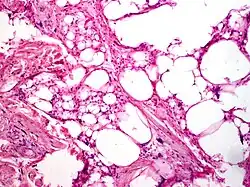

Histologically, bland spindle mesenchymal cells and mature fat make up the majority of the tissue in pleomorphic lipoma. Furthermore, multinucleated large cells with radically positioned nuclei in a "floret-like" pattern are strewn among the spindle cells. The histological spectrum is rather diverse, ranging from a tumor that primarily consists of spindle cells with only a few fat cells to a tumor that resembles an average lipoma with few spindle cells. Cytologically, multinucleated large cells feature irregular, hyperchromatic, and considerably unusual nuclei, while spindle cells have single elongated hyperchromatic nuclei and inconspicuous nucleoli. The two cell types' mitoses are uncommon. Collagen bands that resemble ropes are sporadically spaced throughout the cellular components and are typically a crucial diagnostic indicator for pelomorphic lipoma.[10]